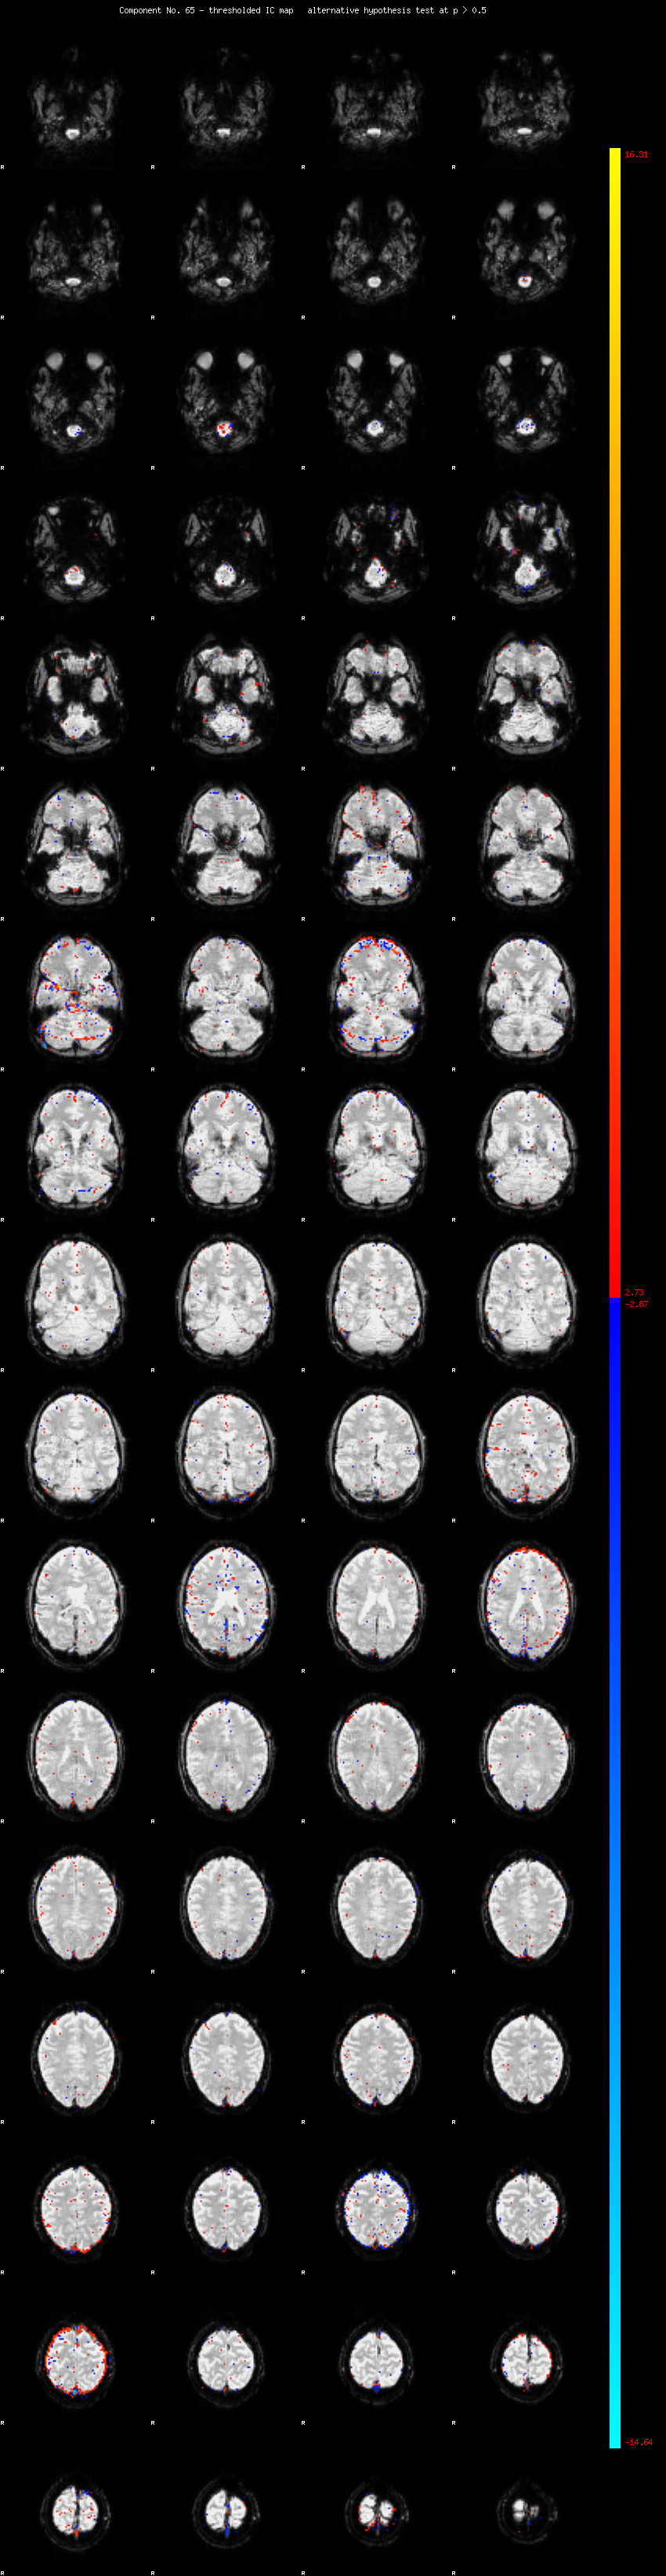

MELODIC Component 65

0.84 % of explained variance;     0.56 % of total variance